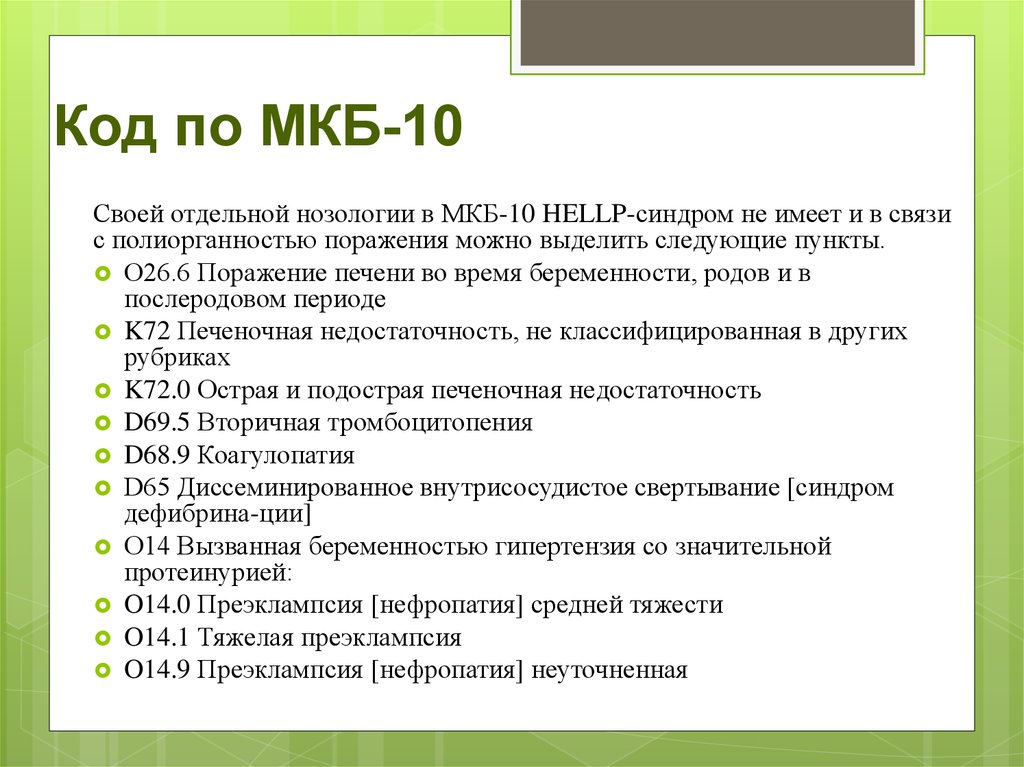

Код мкб 10 атерома головы

Код мкб 10 атерома головы 109 фото